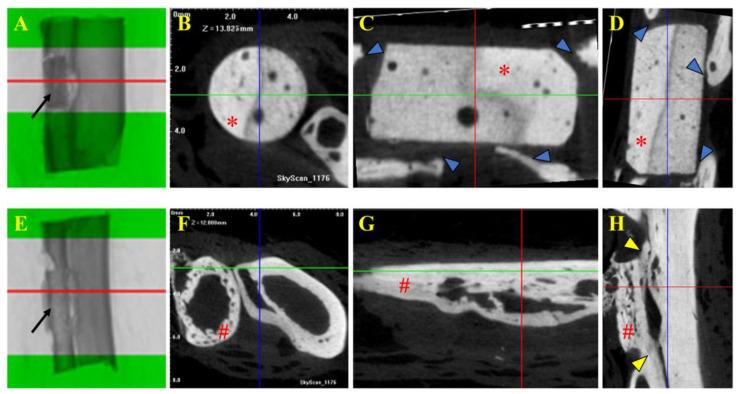

Autografts, allografts, and synthetic bone substitutes are essential in reconstructive orthopedic surgery. Although autografts and allografts provide excellent skeletal integration, their use is limited by host morbidity and graft acquisition challenges. Synthetic materials like β-tricalcium phosphate (β-TCP) offer promising osseoconductive properties as a potential substitute. This study evaluated the osseointegration of β-TCP ceramic cylinder implants in bone defects in rabbits. Eighteen New Zealand rabbits underwent radial diaphysis ostectomy to create a critical segmental defect and were divided into three groups: Group A received β-TCP blocks, Group B received allogenous cortical bone grafts, and Group C underwent ostectomy without defect filling. Postoperative assessments included clinical evaluations, radiographs, micro-computed tomography, and histology at various time points to assess osseointegration and implant resorption. At the 120th postoperative day, Group B showed successful bone integration without infection. In contrast, Group A showed no osseointegration or resorption of the β-TCP implants, and Group C exhibited bone non-union. While β-TCP demonstrated biocompatibility, it lacked osseoconductivity, likely due to low porosity. β-TCP implants did not promote bone consolidation, suggesting that further research on porosity and shape is needed to improve their suitability for veterinary orthopedic reconstructive surgery.

自体骨移植、异体骨移植和合成骨替代物在骨科重建手术中至关重要。尽管自体骨移植和异体骨移植能实现良好的骨骼整合,但它们的应用受到宿主发病率和获取移植物挑战的限制。像β-磷酸三钙(β-TCP)这样的合成材料作为潜在替代物具有良好的骨传导特性。本研究评估了β-TCP陶瓷圆柱植入物在兔骨缺损中的骨整合情况。18只新西兰兔接受桡骨干中段截骨术以制造临界节段性缺损,并分为三组:A组接受β-TCP块,B组接受同种异体皮质骨移植,C组进行截骨术但不填充缺损。术后评估包括在不同时间点进行临床评估、X线片、微型计算机断层扫描和组织学检查,以评估骨整合和植入物吸收情况。术后第120天,B组显示成功的骨整合且无感染。相比之下,A组未显示β-TCP植入物的骨整合或吸收,C组表现为骨不连。虽然β-TCP表现出生物相容性,但其缺乏骨传导性,可能是由于孔隙率低。β-TCP植入物未促进骨愈合,这表明需要对孔隙率和形状进行进一步研究,以提高它们在兽医骨科重建手术中的适用性。